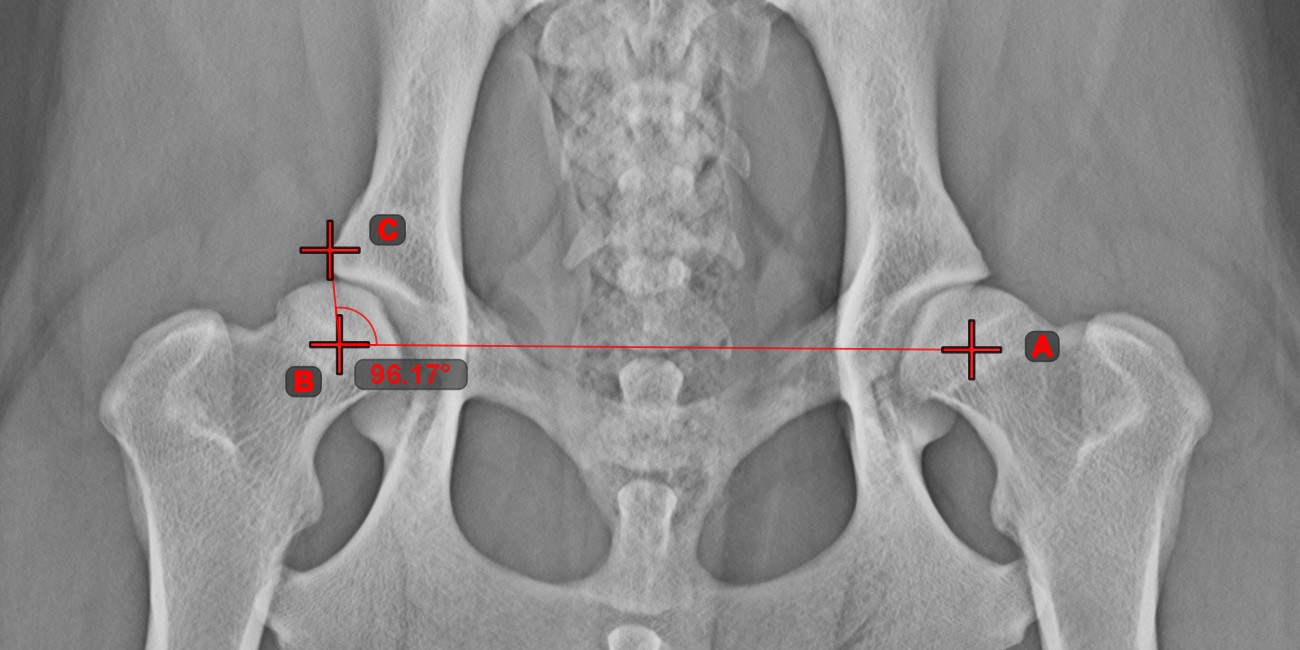

Angle from 3 Points¶

The Angle from 3 Points tool is a simple and effective way to calculate an angle from just three points.

Start by selecting the tool from the left toolbar and assign it to one of the available mouse buttons. Place the start point of the initial side, the vertex, and the end point of the terminal side of the angle, or select the points from the scene. The sides of the angle will be automatically constructed, thus calculating the angle between the lines.

Modify the position of the three points to change the arc of the angle by using the Select/Move Item tool.